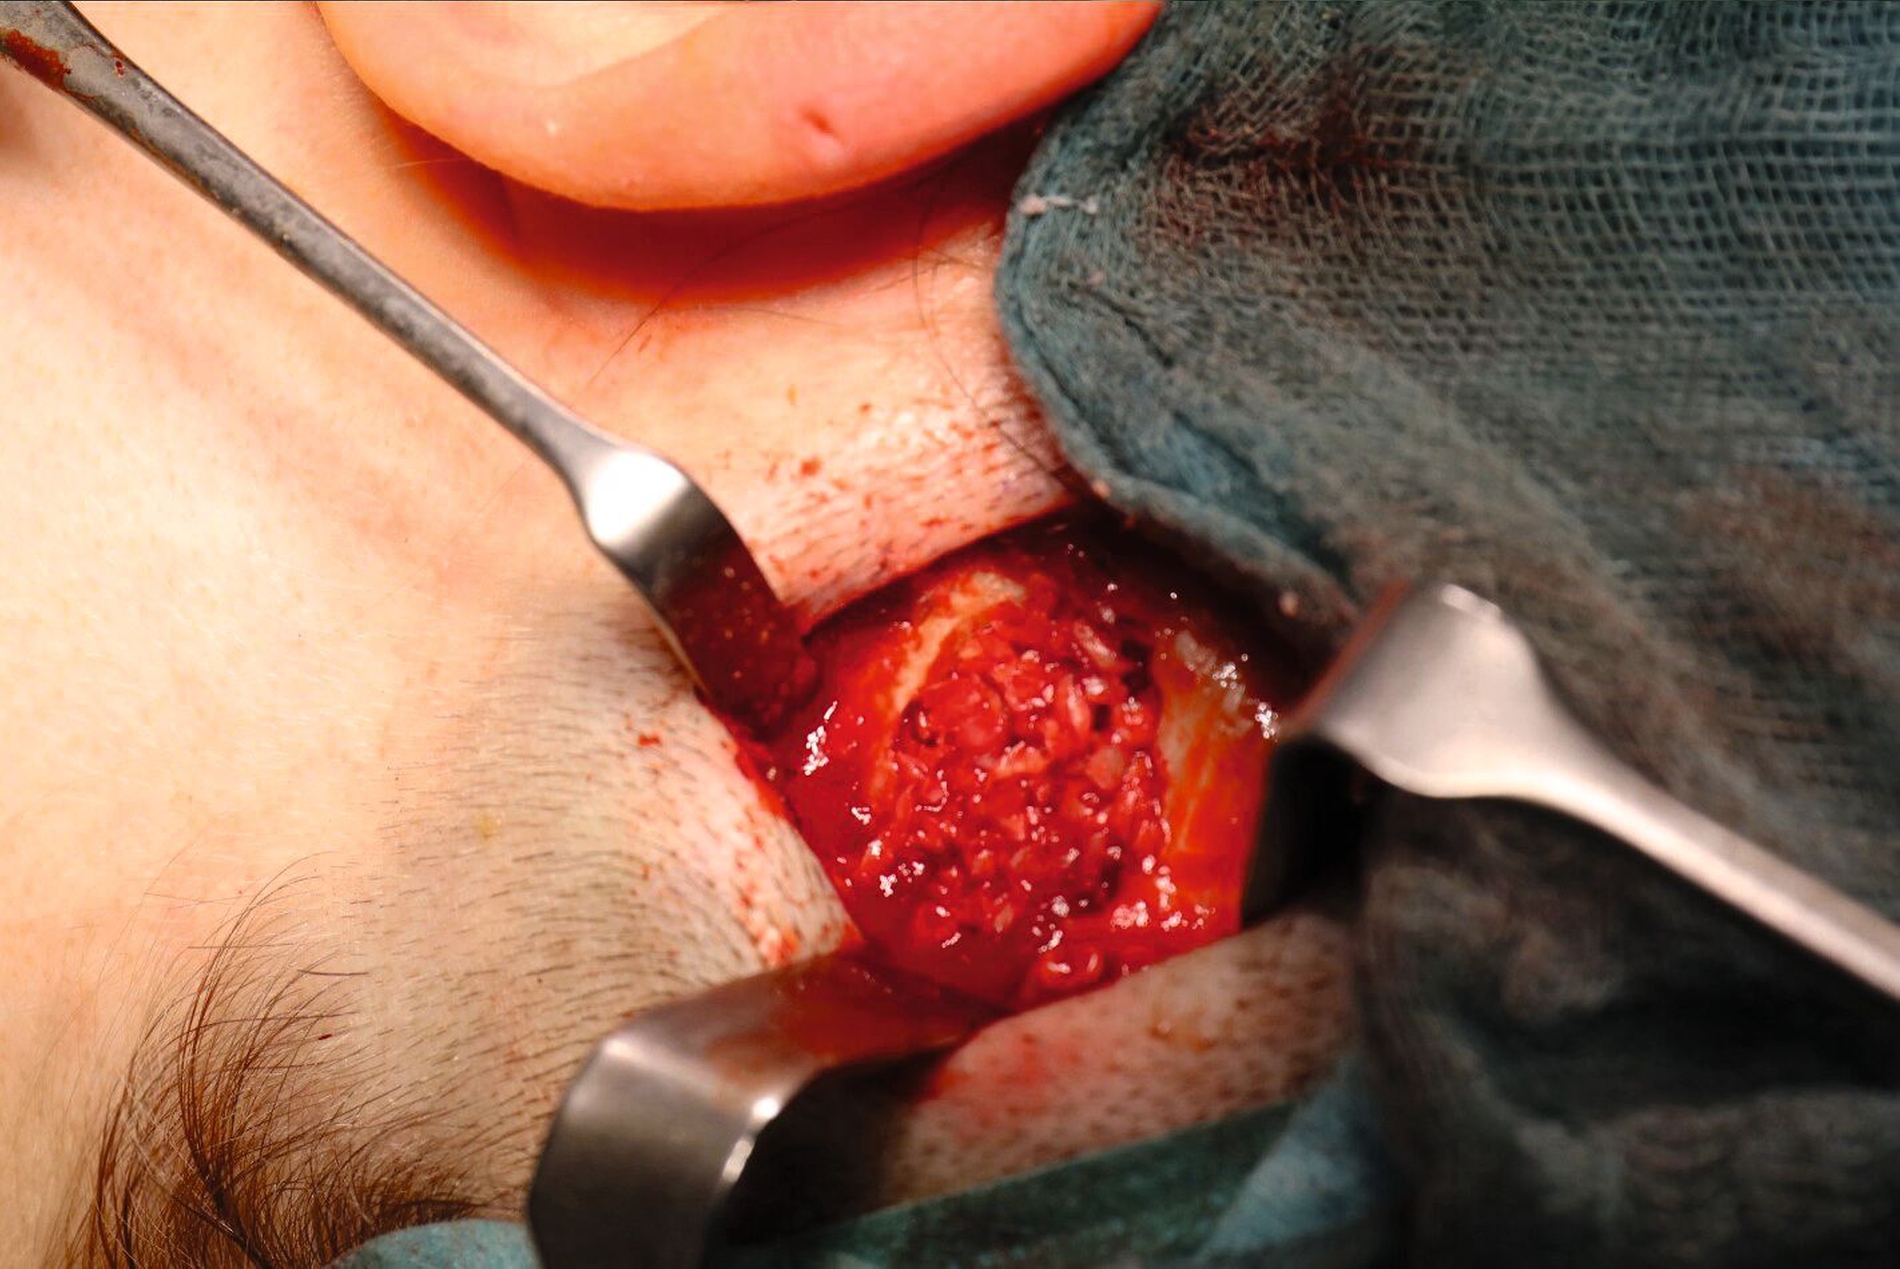

Zwei Wochen später erfolgte in Intubationsnarkose die Resektion der Raumforderung. Nach einer Rasur des Operationsgebiets erfolgte die spindelförmige Schnittführung mit einer maximalen Ausdehnung von 4 cm x 1 cm. Hierdurch konnte nicht nur der fragile Zystenbalg besser erfasst werden, sondern auch eine ästhetisch zufriedenstellende Korrektur der – nach Entfernung der Zyste – überschüssigen Haut vorgenommen werden.

Es konnte nun ein birnenförmiger Balg präpariert und gelöst werden, bis dessen Fistelung durch die Schädelkalotte sichtbar wurde. Dieser Balg wurde zwischenzeitlich extrakraniell abgetrennt, so dass eine bessere Sicht auf den Situs möglich war. Der Knochen um den Fistelgang wurde gemeinsam mit den neurochirurgischen Kollegen entfernt. Die initiale, relativ kleine Knocheneröffnung wurde zur Darstellung des kompletten intrakalottären Zystenbalgs erweitert. Nach Resektion in toto sowie gründlicher Reinigung wurde zum Verschluss ein Gelatineschwamm (Cursapon®) eingelegt. Dorsal der Trepanation wurde Eigenknochen der Tabula externa mittels eines Safescrapers® gewonnen. Im Anschluss erfolgte der mehrschichtige Wundverschluss.